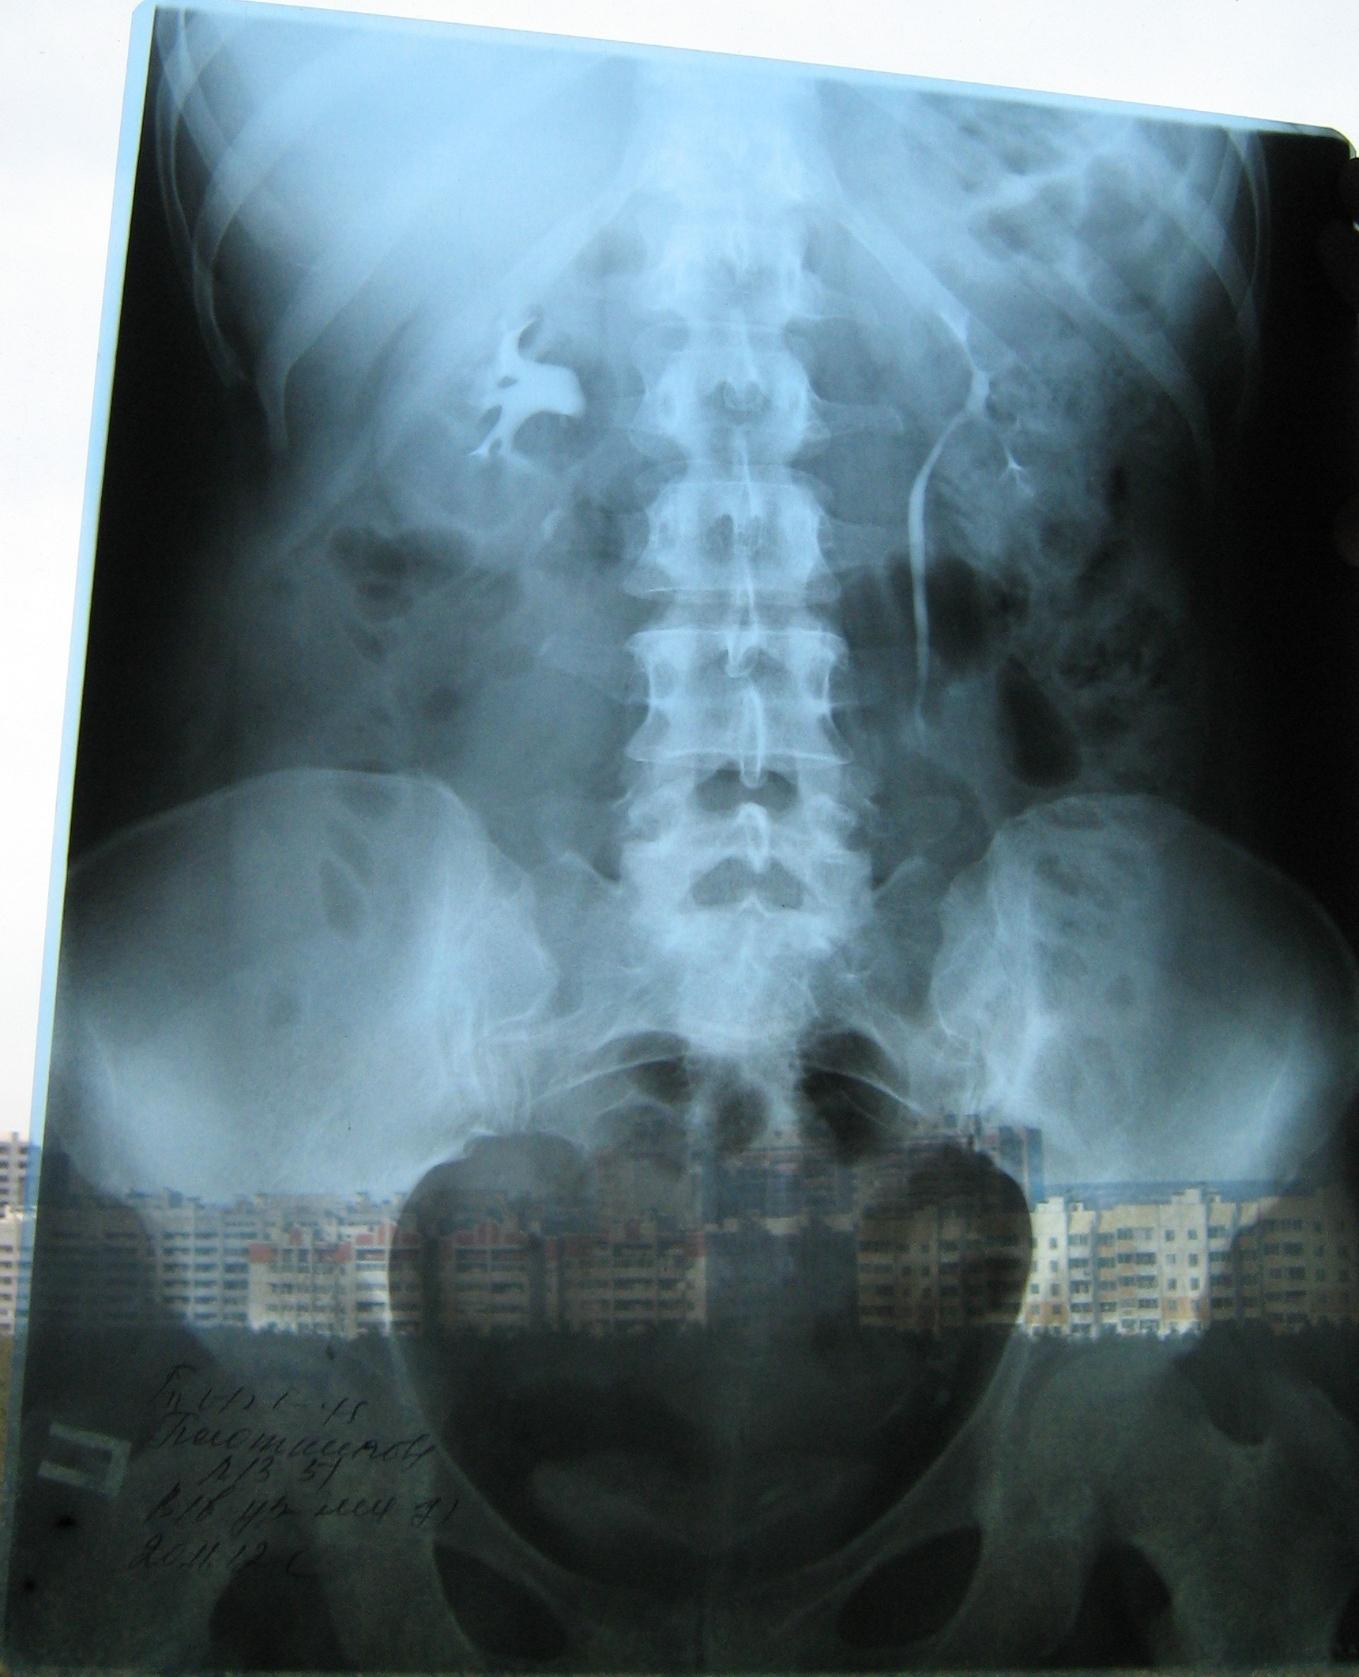

Была сделана операция 04.07.2012г по поводу нефропексии правой почки поясничной мышцей с помощью разреза. После операции болит правая сторона живота и в спине и в пояснице был затронут нерв, и до сих пор правая нога до колен не отходит спереди и сбоку. Через полтора месяца после операции образовался отек, пошло воспаление сзади на спине, потому что был затронут нерв. Сделала урографию через 4 месяца после операции. Если вас не затруднит, посмотрите пожалуйста снимки, правильно ли располагается мочеточник правый после операции. Скажите пожалуйста, посмотрев мои снимки, правильное ли расположение мочеточника и почему болит правая сторона живота все это время, и каким исследованием теперь после операции проверить что там творится в животе, что там затронуто? Все указывает на то что был затронут нерв, оперирующий врач говорит что не может быть такого, а я уже почти всю ногу правую не чувствую

Снимки прикрепляю

Абсолютно нормальное расположение почки и мочеточника . Но ведь и онемение нижней конечности с положением почки не связано. Есть такое понятие "футлярный синдром"- после вынужденного положения конечности. Проконсультируйтесь с неврологом.